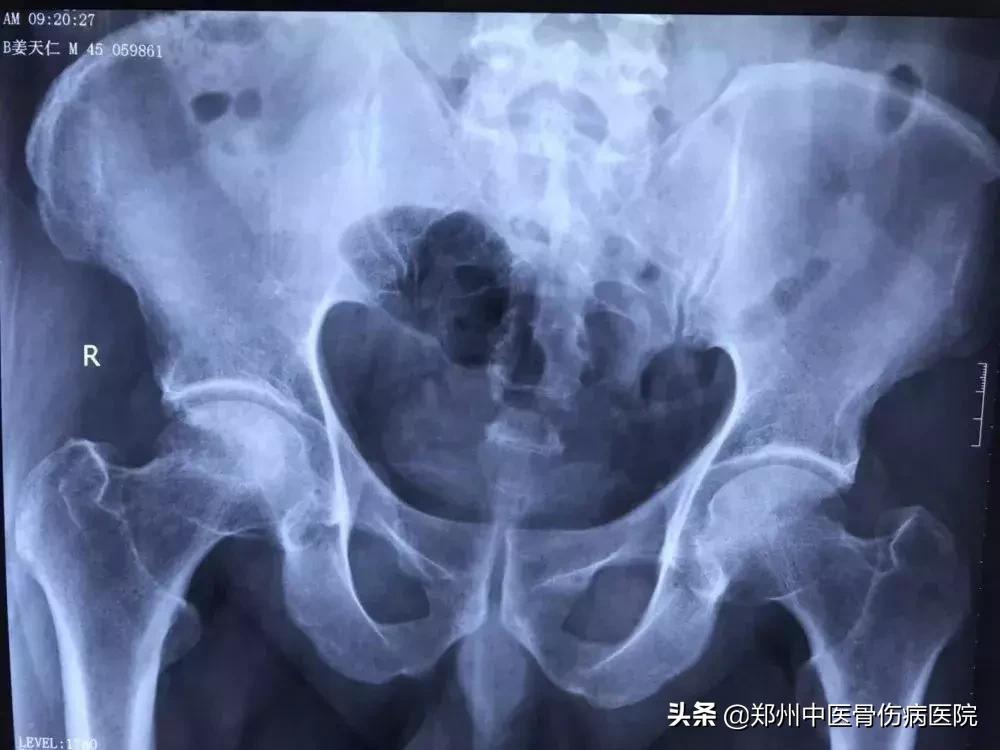

患者片子

2015年6月,姜先生经朋友介绍,慕名前来郑州中医骨伤病医院找到了龚晓霞主任,龚主任在了解病人的基本情况及生活习惯后,通过一系列检查确诊病人为右侧股骨头坏死Ⅲ期。